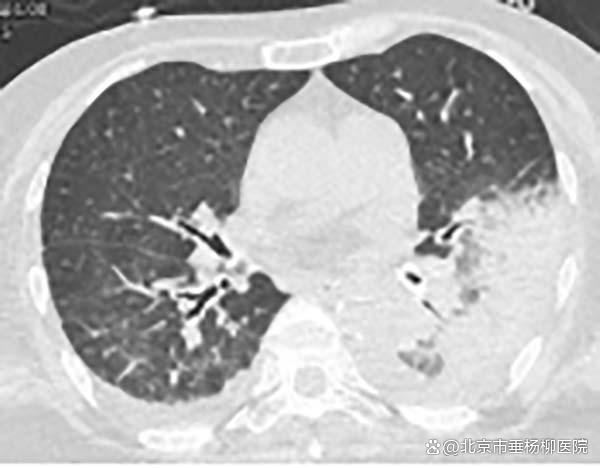

三、胸CT有哪些特点?

胸CT以炎性病变始于单侧肺下叶多见,加重后累及双侧肺叶,上下肺均可受累,主要表现为大片状实变影,可合并小片状磨玻璃影、结节影,以胸膜下分布为主,可见“支气管充气征”“细网格征”“晕征”,常伴胸腔积液,可伴淋巴结肿大。